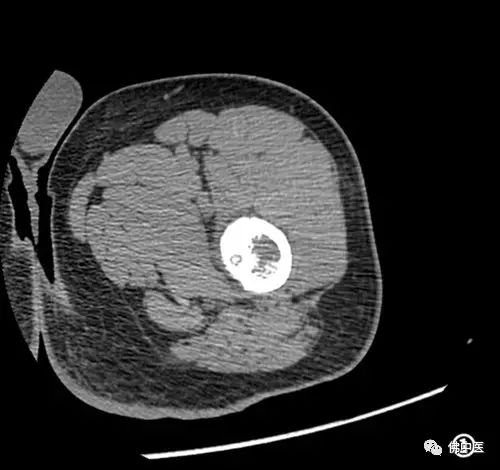

术前CT检查

术中CT照片